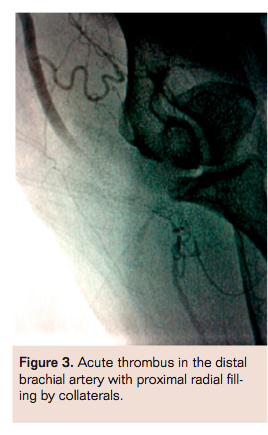

Upper-extremity angiography showed a patent axillary artery. The proximal and mid brachial artery were patent but with slow flow. At the distal brachial artery, there was 100% occlusive thrombus extending into the proximal radial, with filling of the radial artery via small collateral from the brachial artery (Figure 3). There appeared to be only one-vessel radial run-off to the hand. There was almost absent flow to the wrist and hand. The ulnar artery was never visualized. Left heart catheterization showed patent left anterior descending stent and no other significant disease.